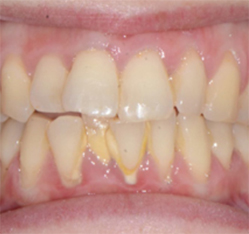

צפיפות מוגדרת כאשר ישנה חפיפה בין שיניים (האחת על גבי השנייה) ולרוב, רוחב קשת השיניים קטן מרוחב השיניים